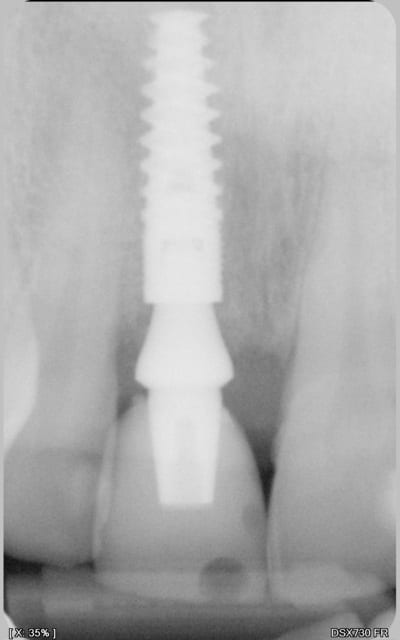

Il s'agit d'une EIIMCI avec comblement du gap.

J'ai utilisé un pilier plein que je n'ai pas déposé depuis la chirurgie.

Aurait-on obtenu le même résultat avec un pilier transvissé?